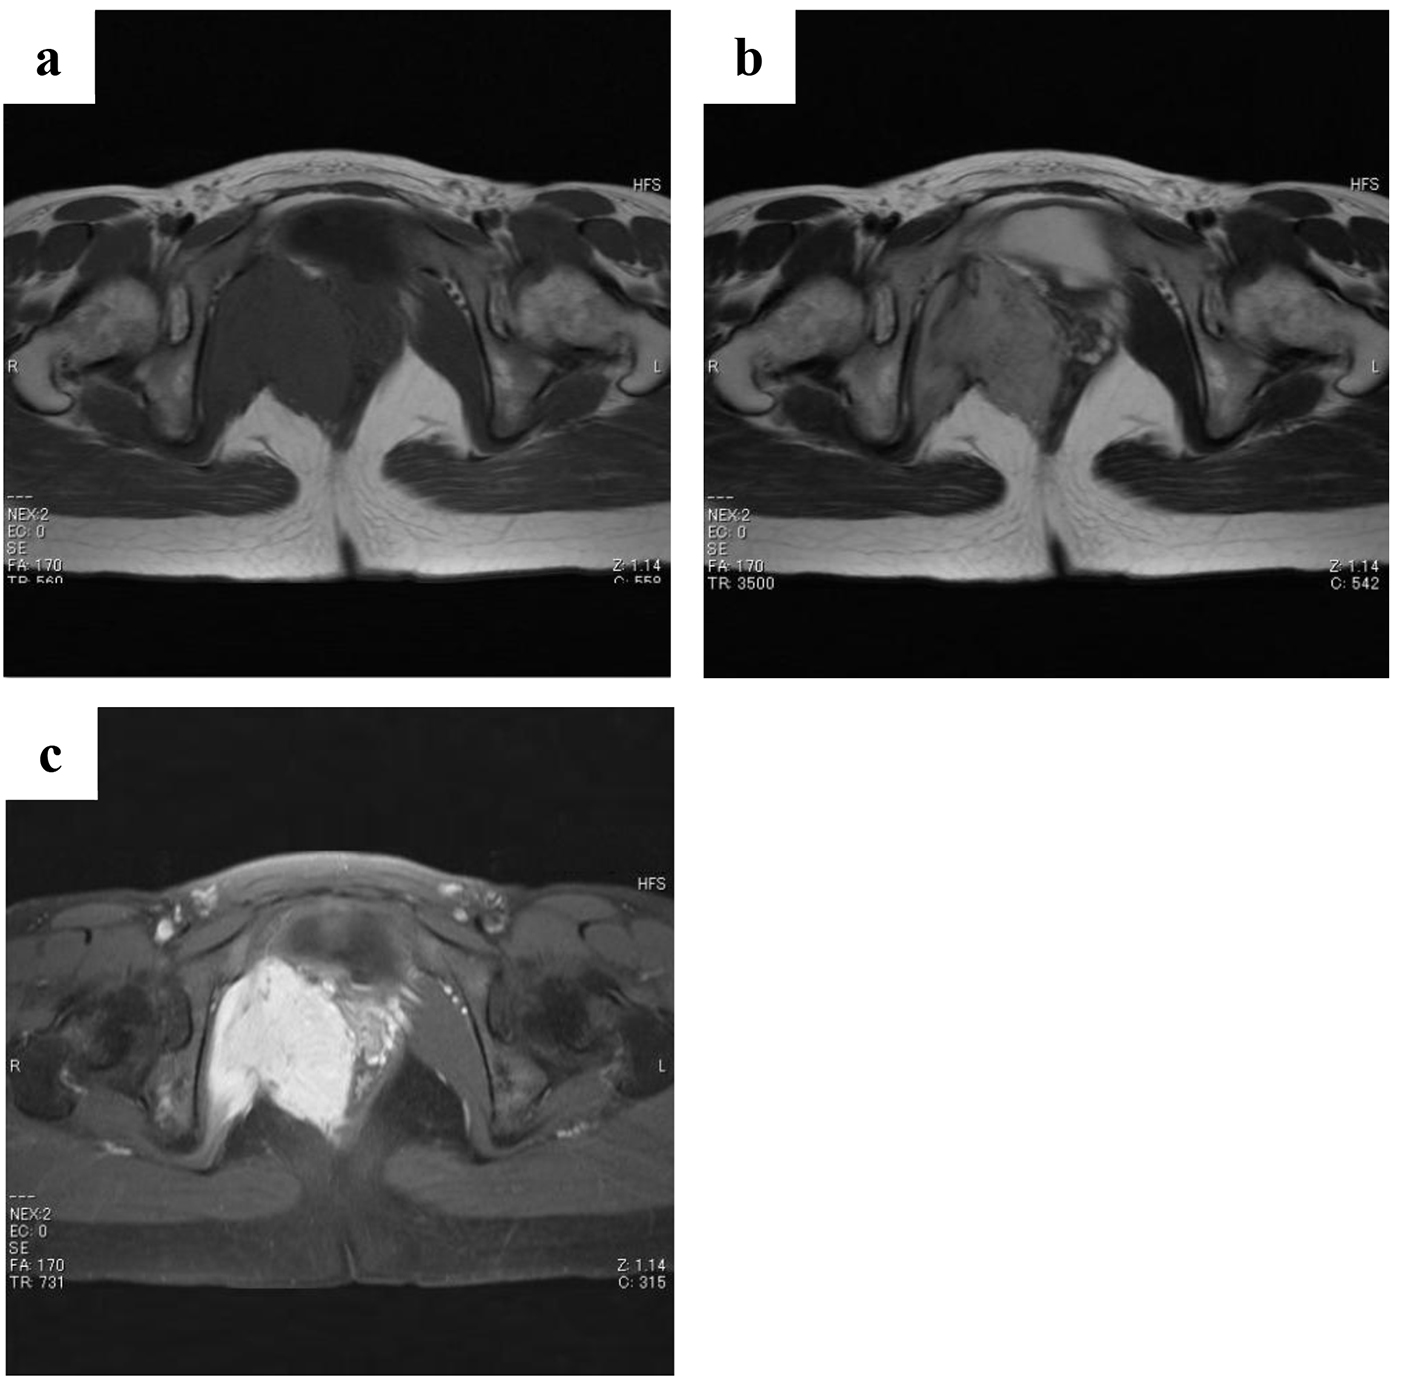

Figure 1. Magnetic resonance images obtained at first examination. There is an enhanced mass (8 cm in diameter) attached to the urinary bladder arising from the internal obturator muscle. The tumor shows a moderately low signal intensity comparable to skeletal muscles on T1-weighted images (a), a moderately high signal intensity on T2-weighted images (b), and high enhancement with a partially mottled pattern after intravenous administration of gadolinium contrast agent (c).